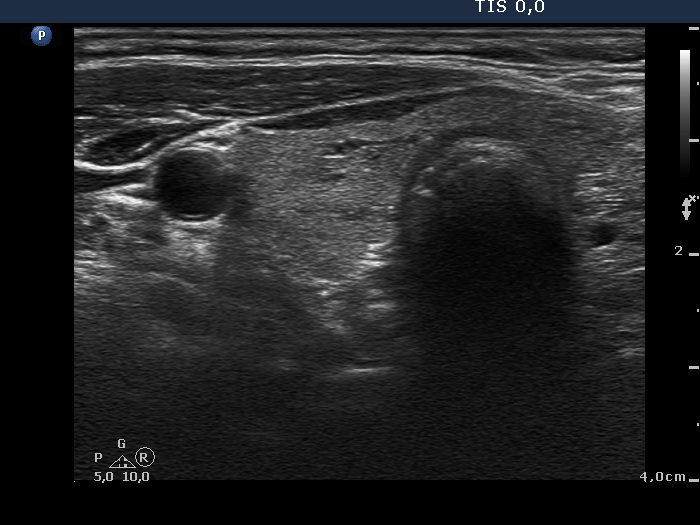

Ultrasonography. The thyroid was echonormal. There were several insignificant lesions in the right lobe. The left lobe presented a large nodule composed of discrete hyperechogenic areas. The lower pole of the lobe was clearly visible during swallowing (see video).